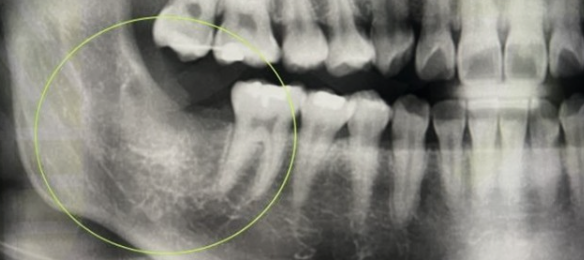

사랑니 발치는 일반 치아와 달리 신경과 가까이 있어 신경 손상 가능성이 있습니다. 하지만, 사랑니 발치를 해야 하는 경우 위험 부담이 있더라도 사랑니를 빼게 됩니다. 제3대구치라고도 불리는 사랑니는 어금니 맨 끝 쪽에 위치하고 있고 맹출 시기는 보통 17~21세 사이로 알려져 있습니다.

구강 내 모든 치열이 완성되고 뒤늦게 자라나는 사랑니는 제대로 맹출 되는 사람도 있지만, 옆으로 누워서 나거나 매복 상태로 통증만 지속되는 경우가 많습니다. 사랑니의 맹출 상태, 관리 방법에 따라 영구치로 유지하는 경우와 발치해야 하는 경우로 나뉩니다.

2022년 사랑니 발치 비용 사랑니 발치는 위치, 맹출 상태, 치아 뿌리 상태에 따라 5가지 형태로 분류되며 사랑니 발치 비용이 달라집니다.

완전 매복 발치 : 36,600 ~ 37,900원 (2022년 일반 의원급 기준)

치아머리 부분이 치조골에 2/3 이상 매복된 상태로 치조골 삭제 및 치아 분할 술을 같이했을 경우입니다.

사랑니 발치 비용은 난이도에 따라 비용이 달라지며 매복이 심한 경우 발치가 불가능하기도 합니다. 난도가 높은 사랑니 발치 시 CT 장비를 갖춘 병원급 or 대학병원에서 발치하길 권장합니다. 사랑니 발치는 무조건 해야 하는 것은 아니며, 제대로 맹출 되었다면 제3대구치로 사용이 가능합니다.